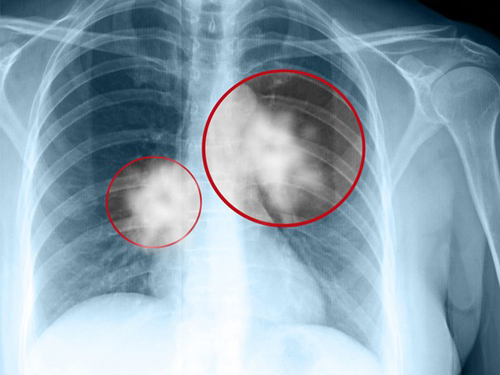

Bệnh ung thư phổi giai đoạn cuối di căn xương. - Ảnh: pinterest.com.au |

Nếu nghi ngờ ung thư phổi, bác sĩ sẽ chỉ định làm thêm xét nghiệm tế bào trong đờm (quan sát dưới kính hiển vi những tế bào lấy từ mẫu dịch nhầy ở phổi khi ho) là một xét nghiệm đơn giản mà có thể có ích cho việc phát hiện ra bệnh ung thư. Tuy nhiên, muốn chẩn đoán chính xác, bác sĩ phải nghiên cứu mô phổi.

Sau khi xác định tình trạng của bệnh nhân, bác sĩ sẽ tiến hành phân giai đoạn để biết được tế bào ung thư đã lan rộng đến bộ phận nào của cơ thể. Ung thư phổi thường ảnh hưởng đến não hoặc vào xương. Việc tìm ra giai đoạn sẽ giúp cho bác sĩ lập kế hoạch điều trị.